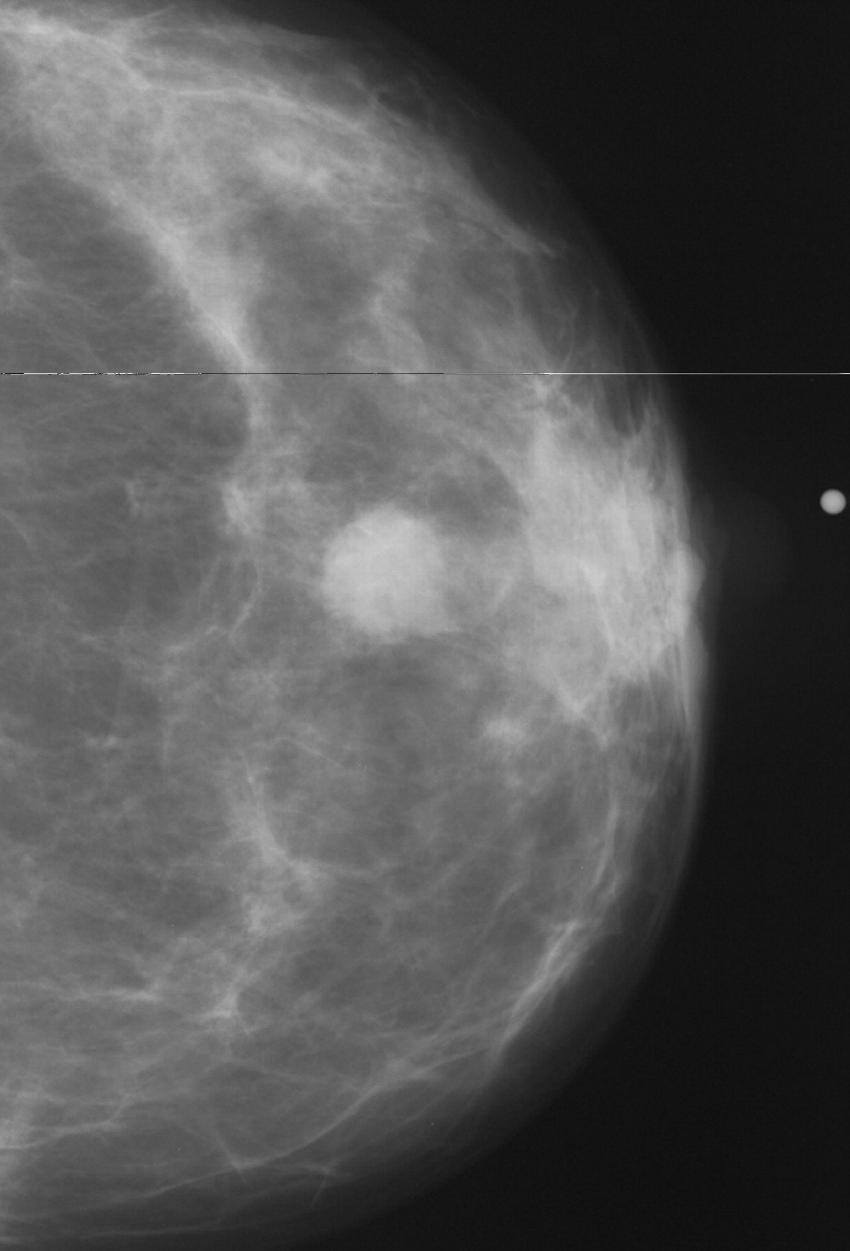

Figure 1. AI enhanced screening mammography.

Figure 2. Example of abnormal mammogram.